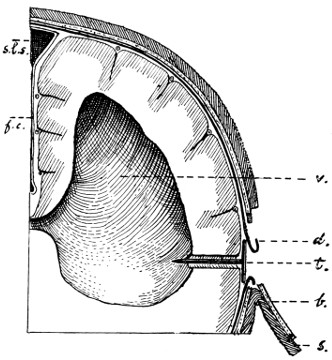

| 74 A and B. To illustrate the extension of disease from the tympanic cavity and the surgical anatomy of that region (after Hunter Tod) | 251 |

| 29 A and B. The base of the skull and the base as seen on transillumination | 70, 71 |

| 50 A and B. The inner aspect of the skull and the same seen on transillumination | 137 |

| 51. To illustrate compression of the brain as produced by an extra-dural hæmorrhage from the middle meningeal artery[x] | 141 |

| 52 A and B. The operative treatment of middle meningeal hæmorrhage | 144, 145 |

| 53. A basic fracture with laceration of both carotid arteries | 148 |

| 54. A basic fracture with laceration of the cavernous sinus | 149 |

| 55. A basic fracture with laceration of both lateral sinuses | 151 |